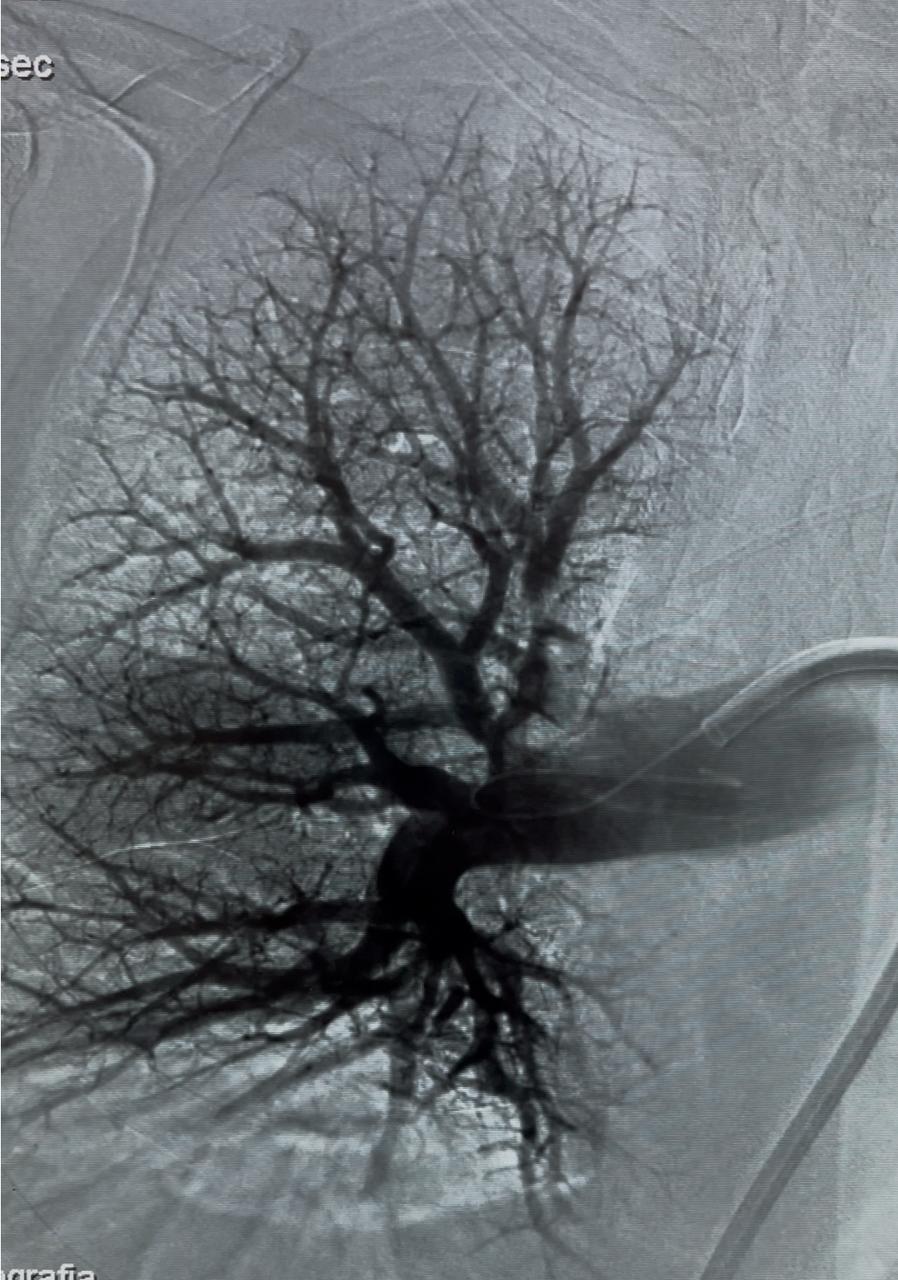

and pulmonary angiography displayed considerable improvement from the beginning of the case (Figure 2).

Figure 2: Right Pulmonary artery post-operative image.